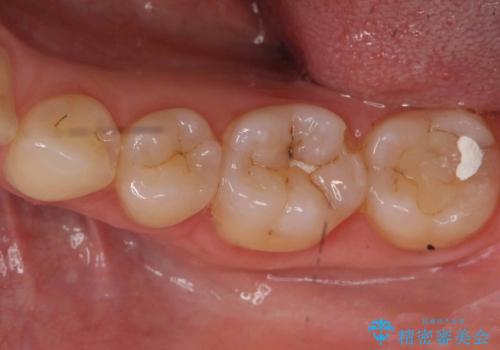

- 詰め物が外れたから作り直しをしたいとのことで来院されました。

外れた状態で日にちが経過していたため、まわりの歯ぐきが歯の上に乗っかっている状態です。

歯ぐきの形を整えてから治療をしていきます。